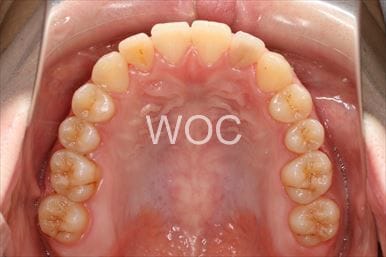

治療前1

治療前2

治療前3

治療前4

治療前5

- 年齢:20歳女性

- 主訴:出っ歯が気になる

- 基本矯正料金:120万円

- 治療期間:1年7ヶ月

- 抜歯部位:上顎両側第一小臼歯